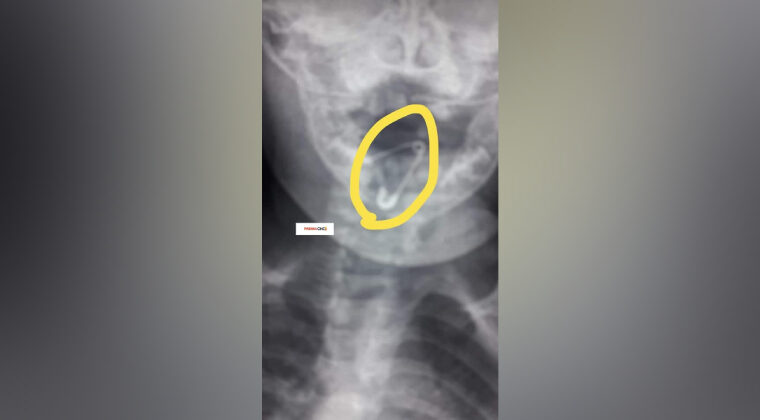

El sábado en horas de la noche, una pequeña bebé de 8 meses tragó un prendedor de alfiler de gancho con la punta abierta.

El objeto quedó atascado en su garganta y sus padres tras percatarse la llevaron rápidamente hasta la unidad de urgencias pediátricas del Hospital Regional de Coronel Oviedo.

Finalmente, lograron dar con la única cirujana pediátrica de la ciudad. La especialista se encontraba en un evento social el que abandonó para atender a la bebé y ayudar a extraer el objeto que podría provocarle una perforación y hemorragia.

Por fortuna, gracias al rápido actuar de las doctoras Eva Peña y Jessica Vargas el objeto logró retirarse con éxito, evitándose que la pequeña fuera trasladada a otro hospital, lo que hubiera tardado mucho tiempo para, posteriormente, someterla a una cirugía.